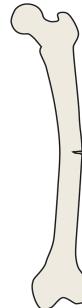

AP/Posterior left femur

- Site: Extra-capsular proximal femur greater trochantric

- Size: 4x3cm apple shaped

- Matrix: Radiolucent,

- Zone of transition: narrow zone of transition

- Bone effect:

- Soft tissue: i cant appreciate soft tissue involvement

most likely benign